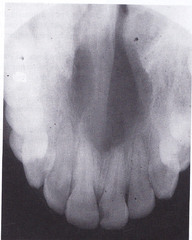

Nasopalatine Canal Cyst

Located between max. centrals or around incisive foramen (occlusal radiograph to see)